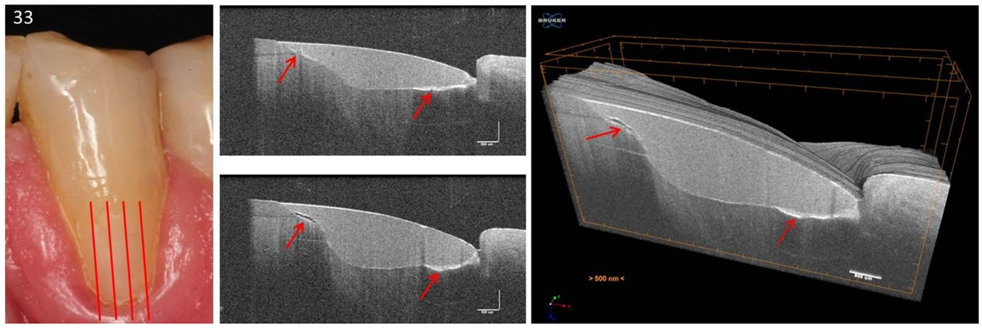

Figure 17.

Tooth 33. 3D scan of a vestibular composite restoration. In the sequence of B-scans of the 3D image stack, restoration irregularities can be displayed, and their progress documented. An extended bond failure on dentin and numerous bubbles in the composite can be seen representing communicating tubes (red arrows). Such irregularities can, for example, lead to marginal or restoration discoloration and restoration loss. In clinical studies, these parameters are used to evaluate restoration systems [24]. The vertical scales are related to refractive index n = 1.0.